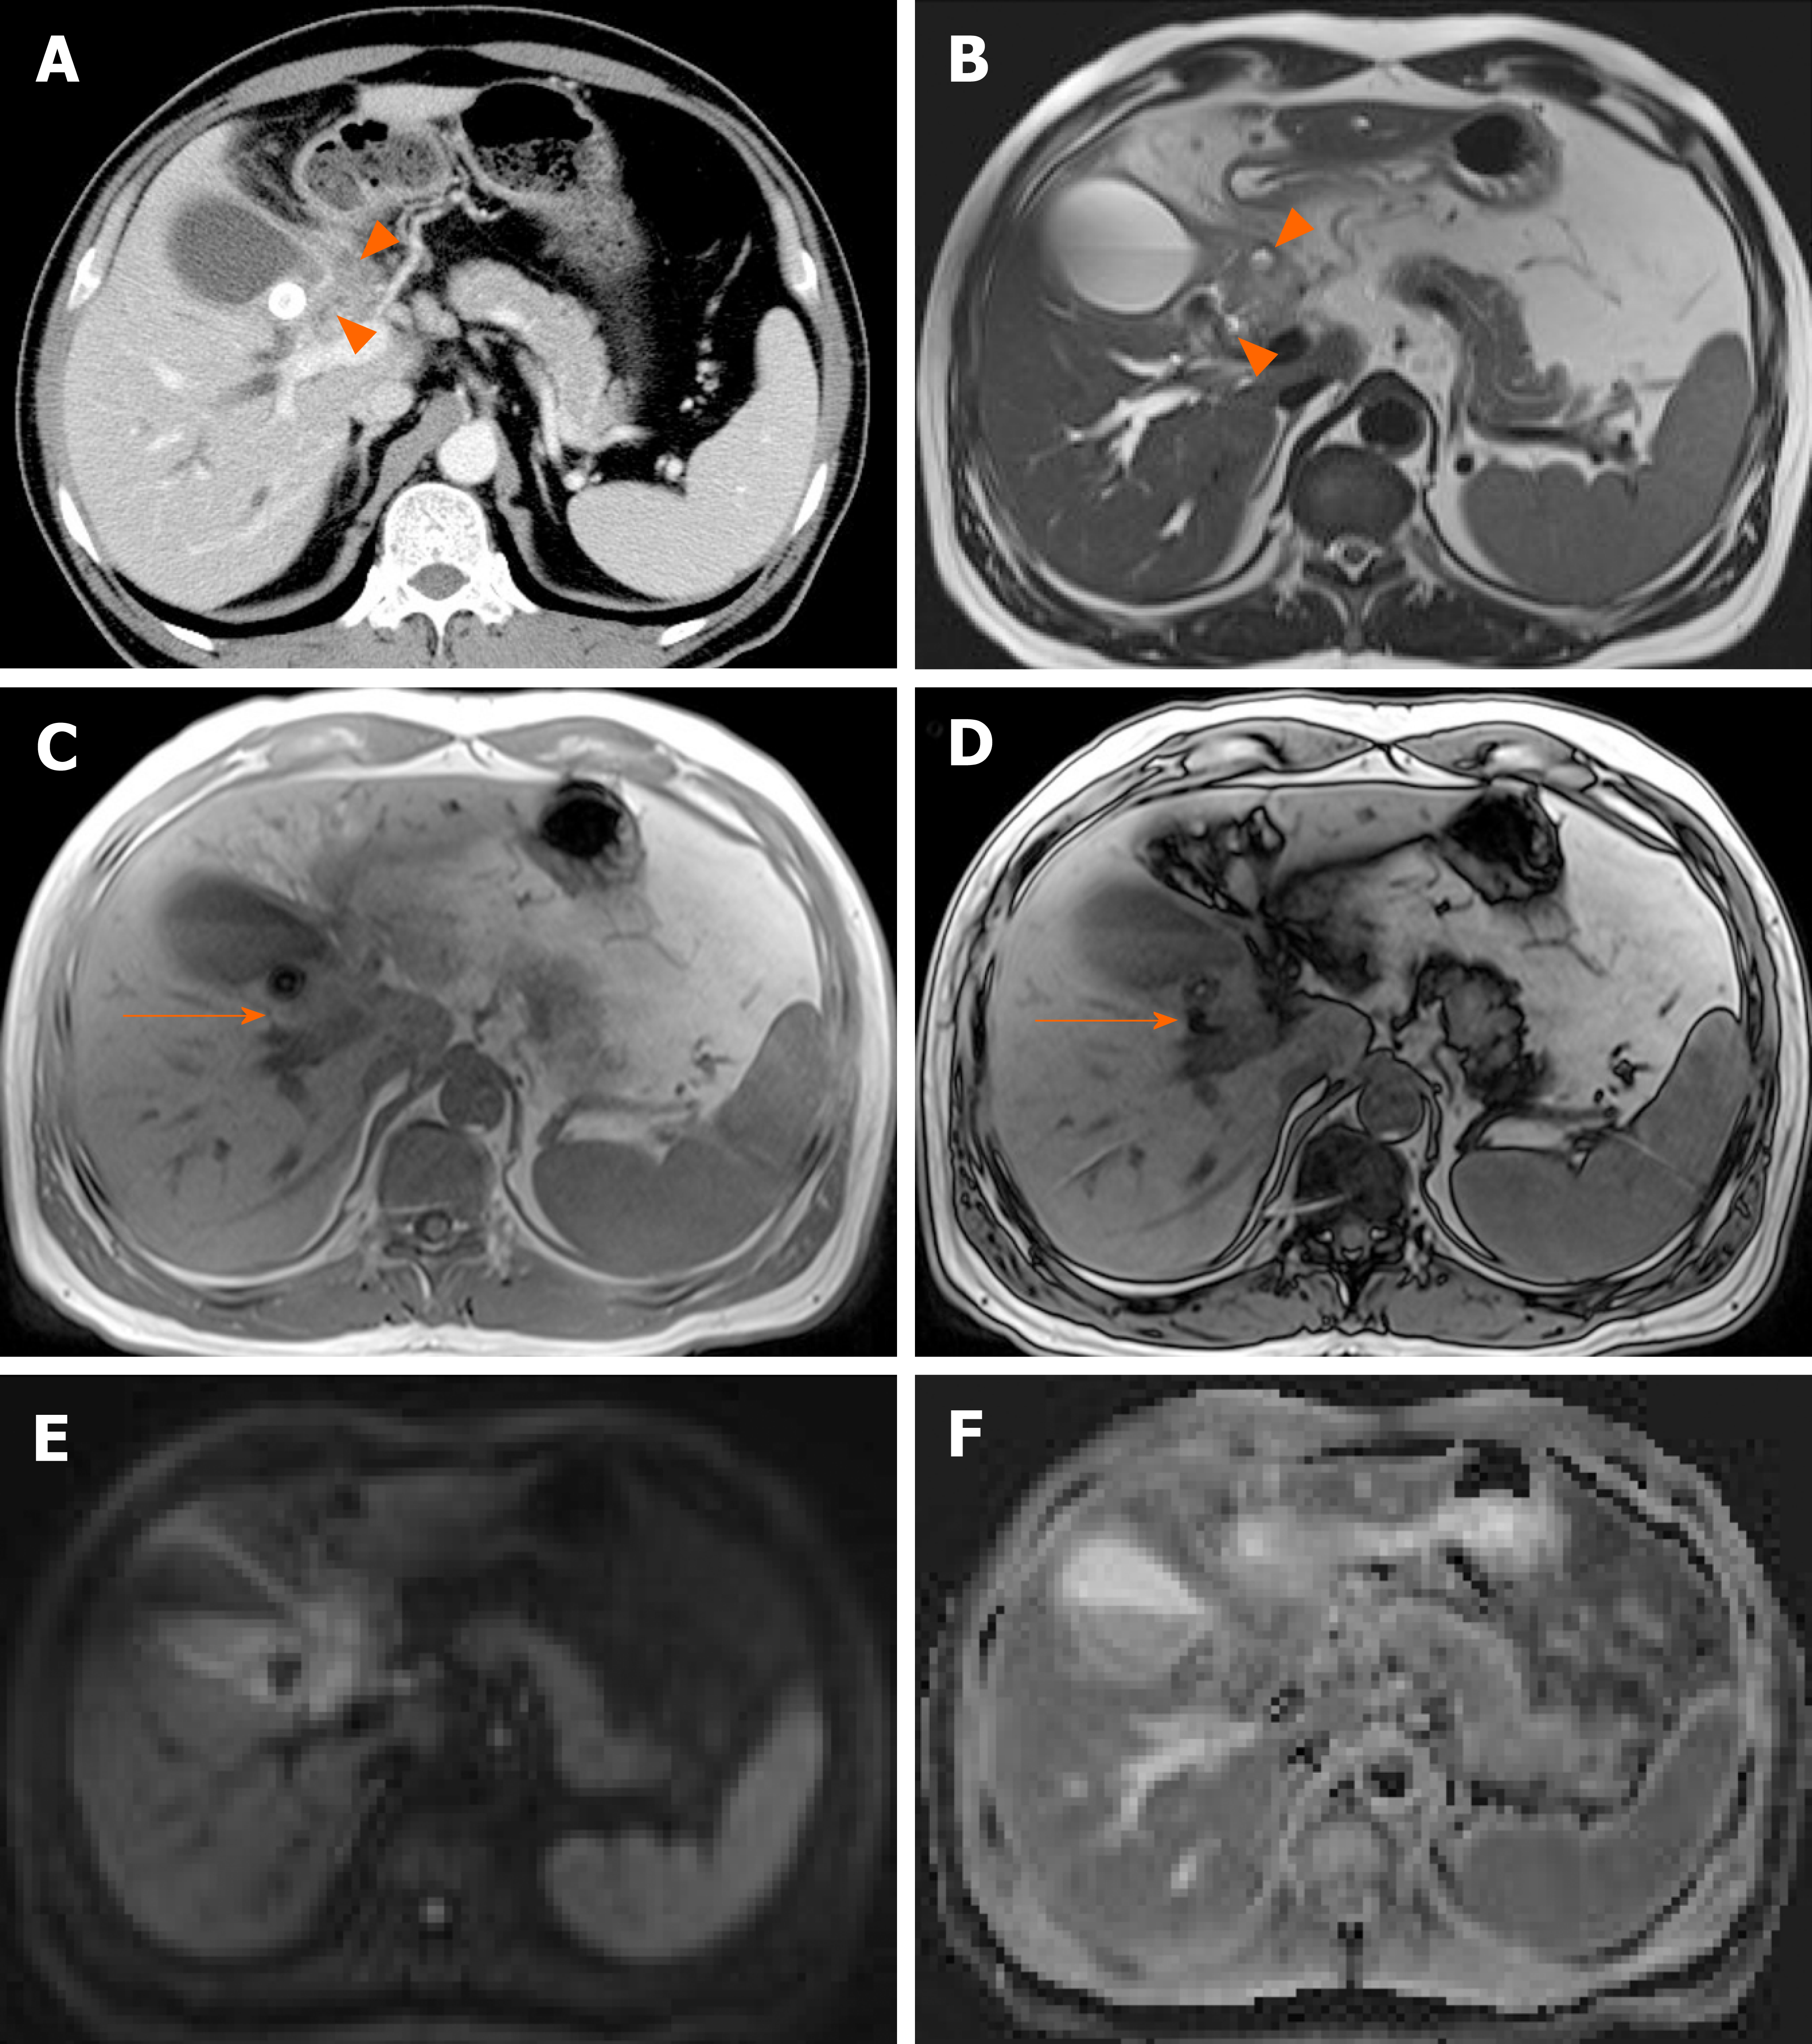

Enhanced MRI showing a bladder tumor at the left wall (arrow). Arrow…

Urinary Bladder Cancer: Role of MR Imaging | RadioGraphics

Bladder carcinoma MRI | Urology News

Bladder cancer MRI – wikidoc

mpMRI of a male patient with stage T1 high-grade bladder cancer 3 …